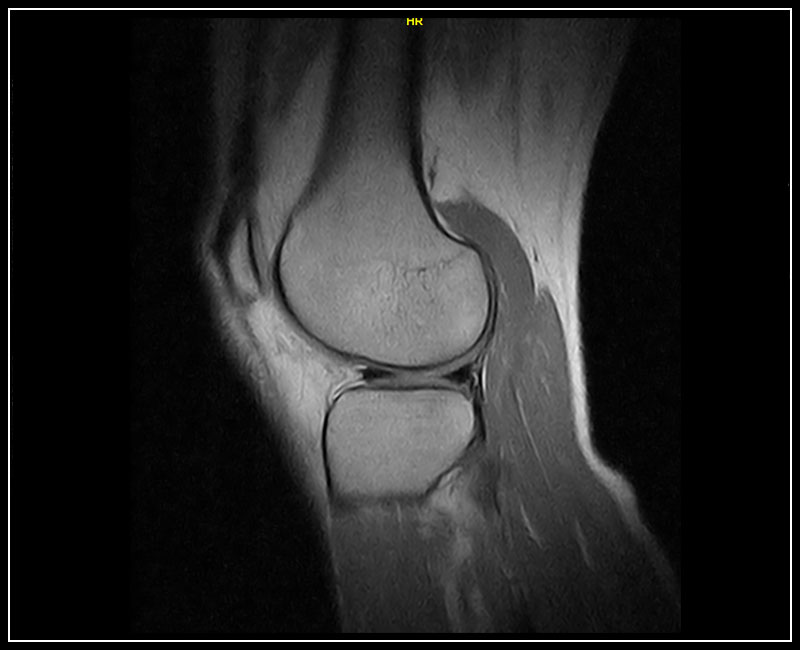

Klinické snímky